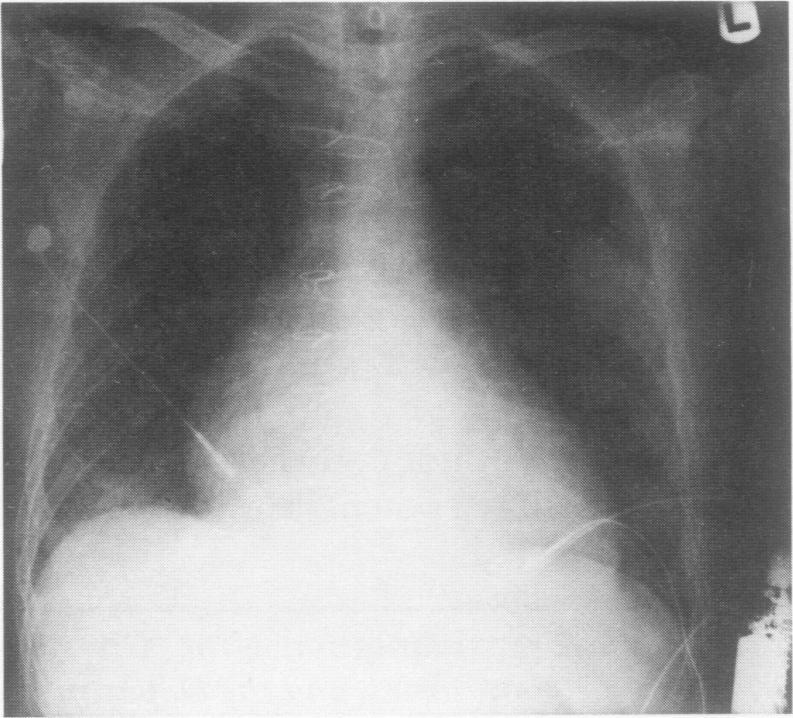

Since July 1982, 18 patients have undergone orthotopic cardiac transplantation at the Texas Heart Institute with steroid and cyclosporine immunosuppression. There have been no deaths from infection despite 15 bacterial, 8 viral, 6 fungal and 1 protozoal infection episodes. With a total follow-up of 90 patient months (mean follow-up, 5.0 months; range 0.1 to 18 months), the incidence of infection is 33 episodes per 100 patient months (1.7 episodes per patient). Only 23 episodes (77%) required drug treatment. Compared to conventional immunosuppressive regimes, cyclosporine treatment is associated with a substantial reduction in the incidence and severity of infection in cardiac allograft recipients.